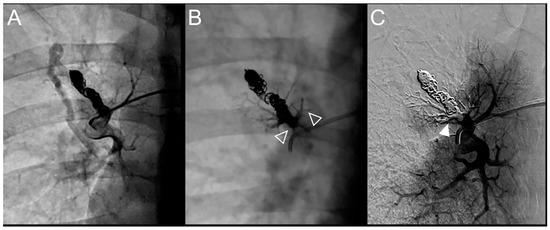

Figure 2.

Case examples of a 68-year-old man (A–C) and 48-year-old man (D–F) treated for a simple recurrent pulmonary arteriovenous malformation. In both cases, digital subtraction angiography unsubtracted images showed a distance >10 mm between the first coil and the aneurysmal sac, which is considered a risk factor for recanalization. (A–C). Embolization was performed using Onyx® (0.3 mL) to fill the afferent artery in and downstream of the pre-implanted coils and resulted in an immediate complete occlusion, maintained after 23 months follow-up. No leak in the aneurysm or in the vein was reported. (A). Opacification of the afferent artery showed a recanalization through the pre-implanted coils (full arrowhead). (B). Opacity within, downstream and upstream of the coils (empty arrowheads) showed the distribution of Onyx® without any evidence of a leak in the aneurysmal sac. (C). Opacification of the afferent artery showed the absence of opacification of the aneurysmal sac and the efferent vein in favor of immediate occlusion. The opacification of the healthy arterial branch did not reveal any perfusion defect. (D–F). Embolization was performed using Onyx® (0.4 mL) to fill the afferent artery in and downstream of the pre-implanted coils and resulted in an immediate complete occlusion, with a recurrence 36 months after the procedure. No leak in the aneurysm or in the vein was reported. (D). Opacification of the afferent artery showed a recanalization through the pre-implanted coils (full arrowhead). (E). Opacity within, downstream and upstream of the coils (empty arrowheads) showed the distribution of Onyx® without any evidence of a leak in the aneurysmal sac. (F). Opacification of the afferent artery showed the absence of opacification of the aneurysmal sac and the efferent vein in favor of immediate occlusion.